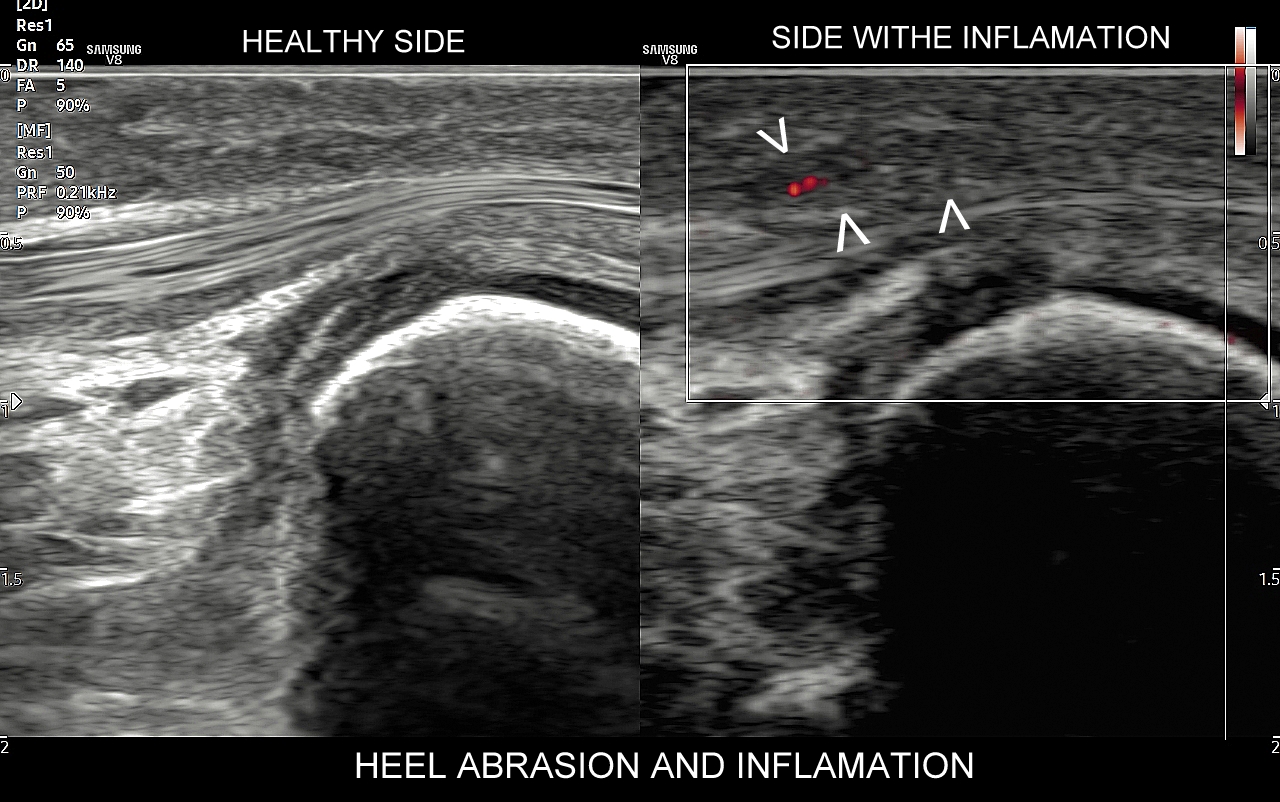

USG jest wysoce przydatną oraz metodą diagnostyczną pierwszego wyboru przy ocenie szeregu zmian chorobowych toczących się w obrębie stopy, w tym urazowych, przeciążeniowych, zapalnych, infekcyjnych, metabolicznych, czy nowotworowych. Przykładem najczęściej występującego urazu stopy, potocznie nazywanego skręceniem kostki występującego w wyniku inwersji stopy, jest naderwanie więzadła skokowo-strzałkowego przedniego (ATFL). Zmiany urazowo-przeciążeniowe dotyczyć mogą jednakże praktycznie każdego elementu. Dr Szczepański diagnozował w USG stopy m. in. takie patologie jak złamanie kości strzałkowej, złamanie trzeszczek, naderwania i zerwania ścięgien, czy przeciążenia troczków. W USG można ocenić również unaczynienie stopy, powikłania stopy cukrzycowej, zapalenie stawów w przebiegu dny moczanowej i reumatoidalnego zapalenia stawów, a także nowotwory stopy, w tym włókniaka rozścięgna podeszwowego (choroba Ledderhose’a).